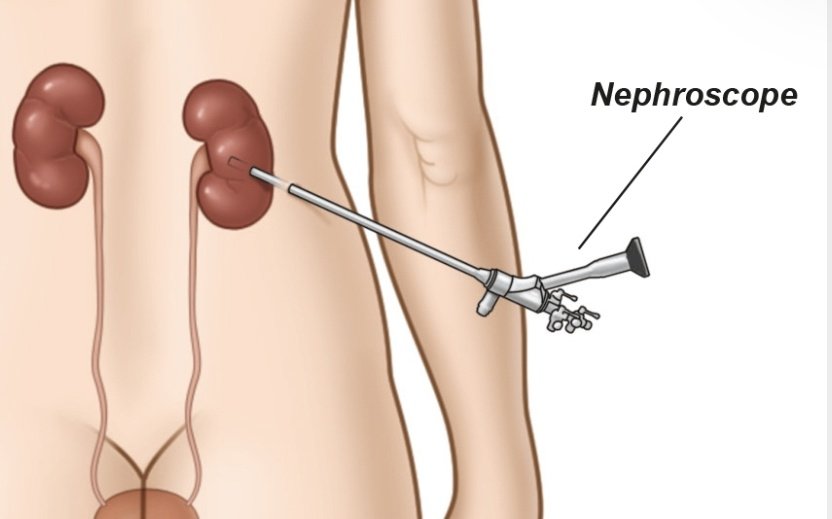

2️⃣ المناظير والتكسير بالليزر..

تعتبر اكثر الطرق استخداما وهي امنه الى حد ما اذا تم عملها من قبل المختصين و لا تحتاج اي شق جراحي .

تعتبر اكثر الطرق استخداما وهي امنه الى حد ما اذا تم عملها من قبل المختصين و لا تحتاج اي شق جراحي .